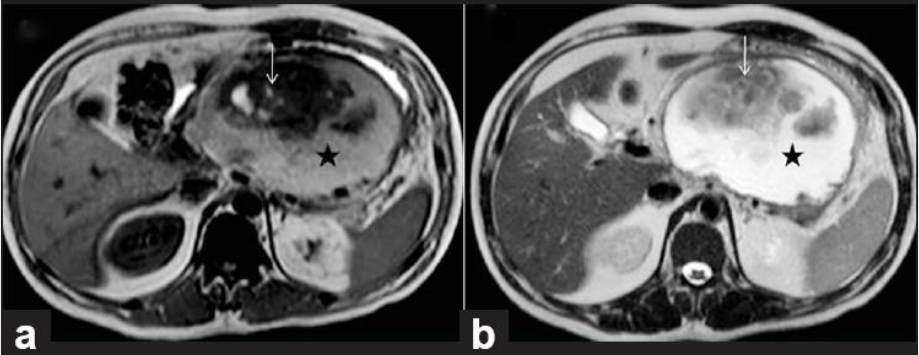

10

Q

מהו הממצא

A

פאנקריאטיטיס כרוני

How well did you know this?